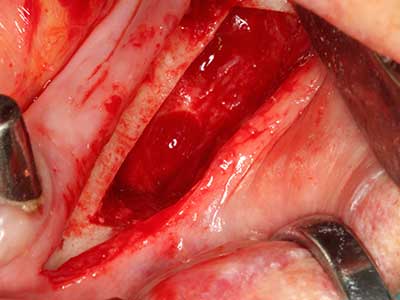

Fig. 19: Surgical site after neurolysis and removal of osteoma.

When surgical procedures are performed on bone in the immediate vicinity of sensitive structures such as blood vessels or nerves, rotary instruments pose a significant risk of iatrogenic injury. Piezoelectric devices can be helpful for preparation of bone covers and removal of hard tissue close to nerves, particularly for exposure of nerves after iatrogenic injury but also during nerve lateralization for resective and reconstructive procedures or implant placement (Fig. 17-20). Light contact between the piezotip and the nerve does not generally result in damage but proceeding incautiously with saw-like motions or attachments where a residual bone substrate remains may cause temporary or even permanent nerve damage. However, the risk of damage is considered to be substantially lower than when using saws or milling instruments (Pereira, Gealh et al. 2014).

Indication: Preparation near nerves